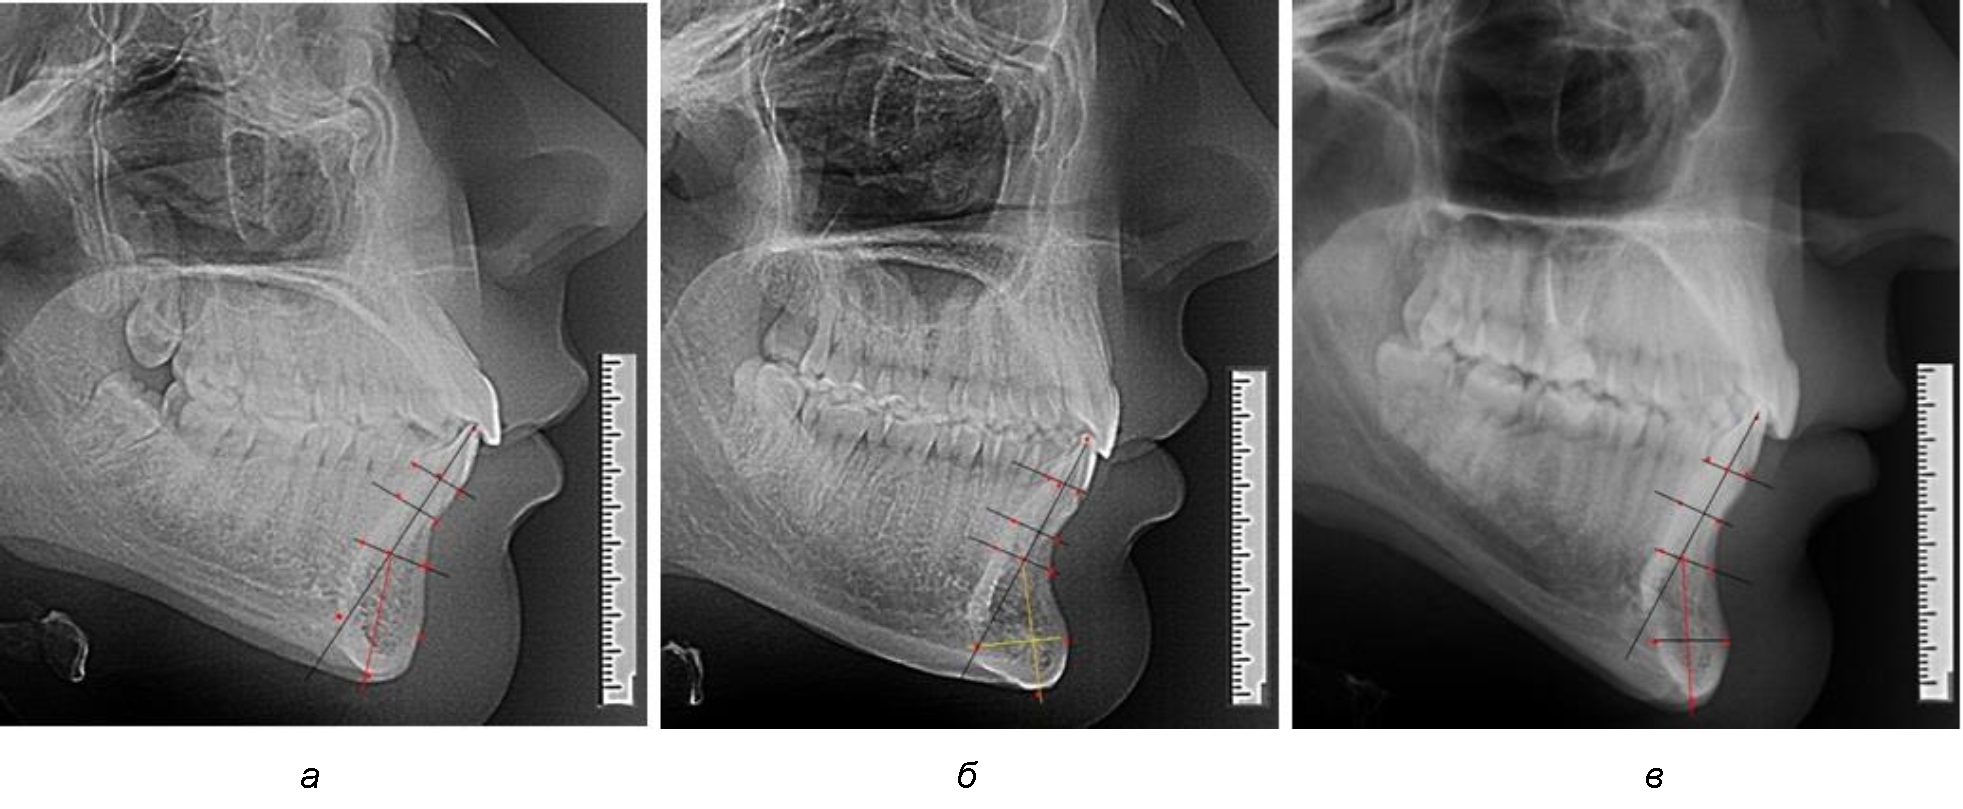

При аномалиях окклюзии в сагиттальном направлении и характерных для них различных вариантах протрузионного и/или ретрузионного патологического положения передних зубов, как правило, сопровождается изменениями параметров подбородочного выступа. Учитывая многообразие форм аномалий окклюзии, параметры подбородочного выступа вариабельны как по сагиттали, так и по трансверсали.

Нередко отмечается деформация подбородочного выступа и различное его положение по отношению к зубоальвеолярной части сегмента. При мезиальной окклюзии нередко нижняя подбородочная точка смещается кзади по отношению к условной срединной вертикали нижнего резца, а при дистальной окклюзии отмечается компенсаторное отклонение подбородка кпереди (рис. 5).

Рис. 5. Особенности нижнечелюстного резцового сегмента на ТРГ у людей при мезиальной (а) и дистальной (б) окклюзии

Кроме того, так же как и у людей с физиологической окклюзией, определялось различие в положении апикальных точек Downs и Schwarz, что, по нашему мнению, может определять тактику лечения патологических форм протрузии/ретрузии резцов с учетом биотипа костной ткани.